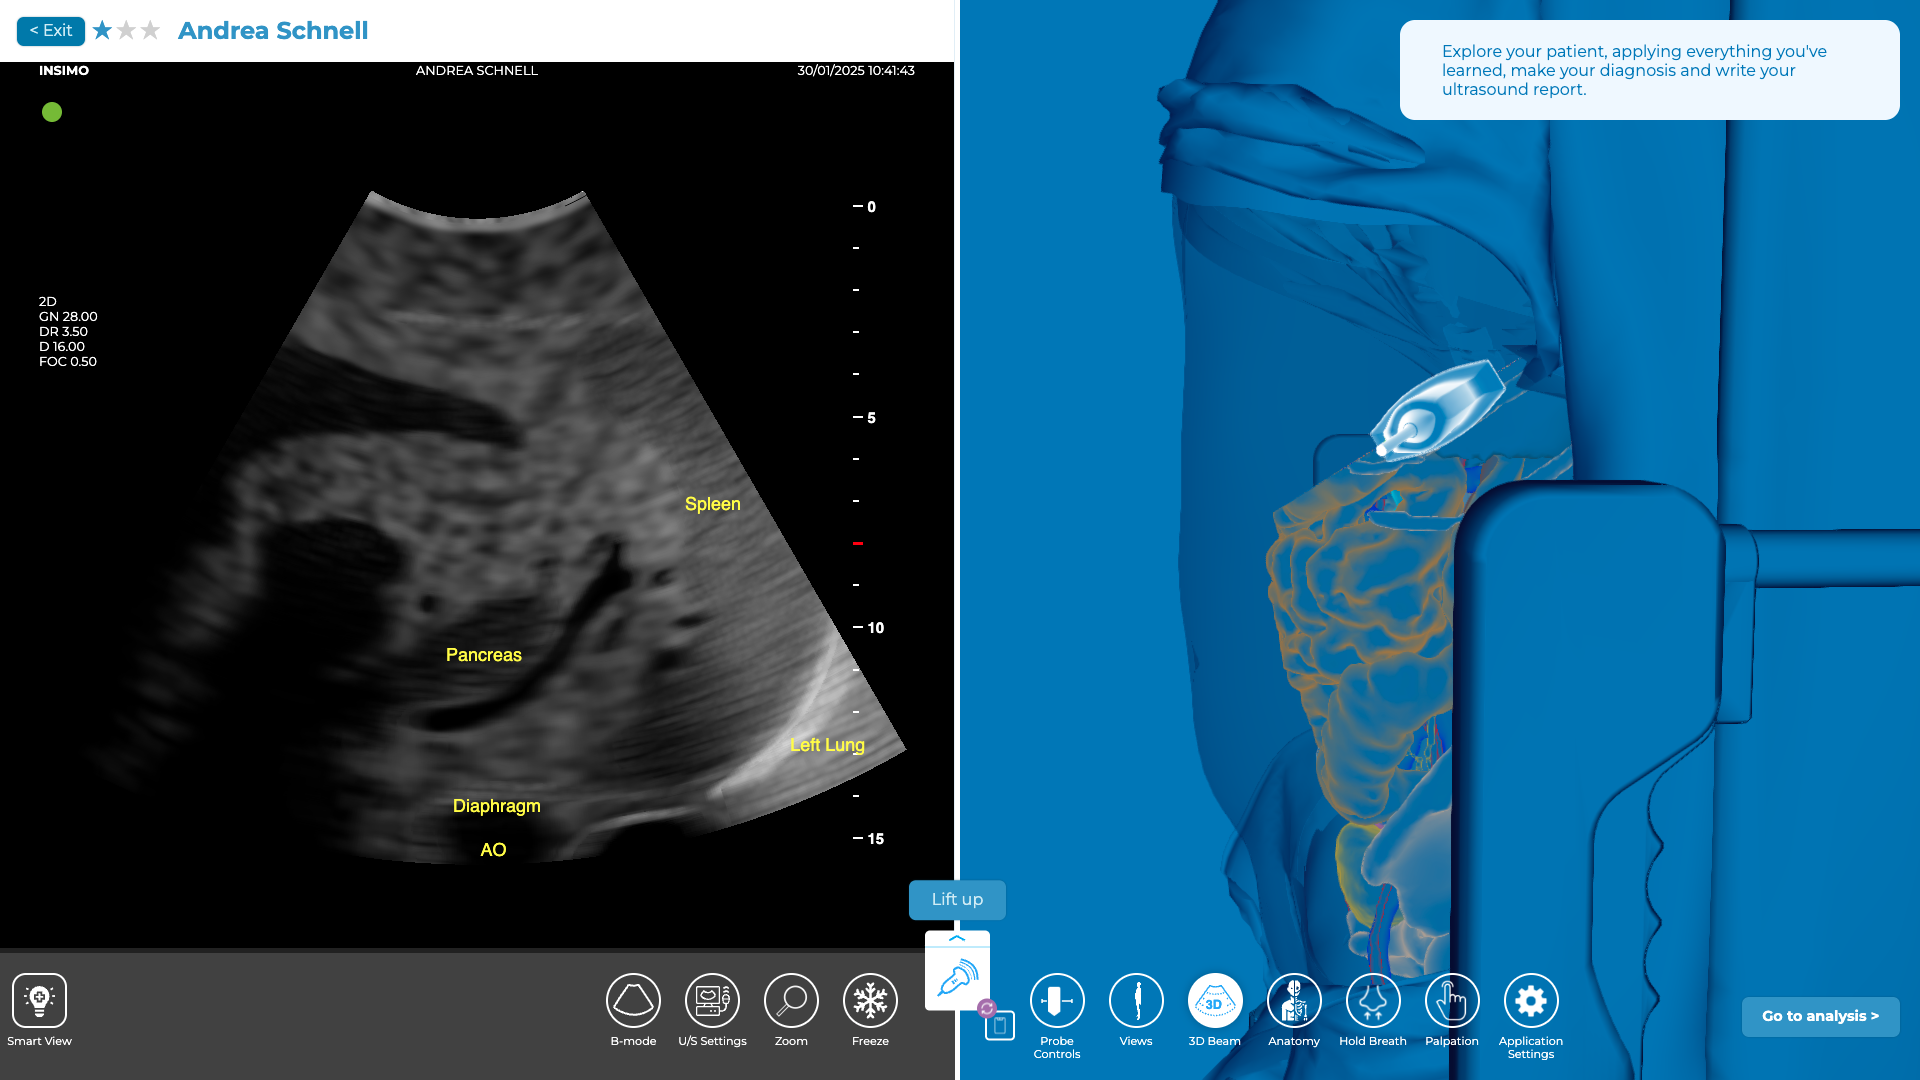

Evaluation du Quadrant Supérieur Gauche (QSG)

Cette partie de l’examen échographique permet d’explorer la rate et le diaphragme gauche. La présence de liquide libre autour de la rate peut signaler un traumatisme splénique, complication fréquente après un traumatisme abdominal [9].

Pour identifier cette zone, vous pouvez utiliser la ligne axillaire antérieure comme repère, tout comme pour le QSD, mais il est important de noter que la cavité abdominale dans le quadrant supérieur gauche est plus haute et plus en arrière. Cela signifie que vous devrez scannez les espaces intercostaux 6 à 10 pour atteindre la zone où la rate et le diaphragme sont visibles et bien explorer cette région [11].

Lorsque vous positionnez la sonde à cet endroit, commencez par repérer la rate. Une fois que vous l’avez visualisée, vous pouvez utiliser cet organe comme une fenêtre acoustique pour explorer les structures environnantes. En suivant la courbure de la rate, vous devriez pouvoir identifier le rein gauche et son interface avec la rate. Cela vous permettra d’évaluer si du liquide libre est présent dans l’espace entre la rate et le rein, ce qui pourrait indiquer un traumatisme splénique.

Exploration du QSG sur diSplay U/S